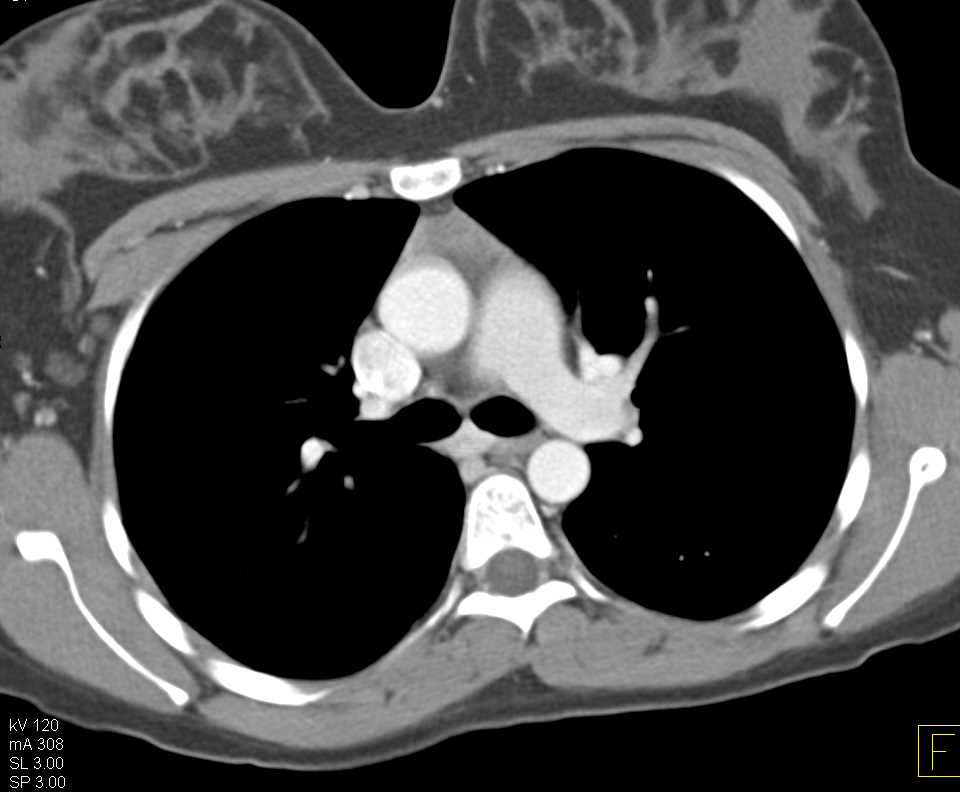

Extensive Aortic Valve Calcification